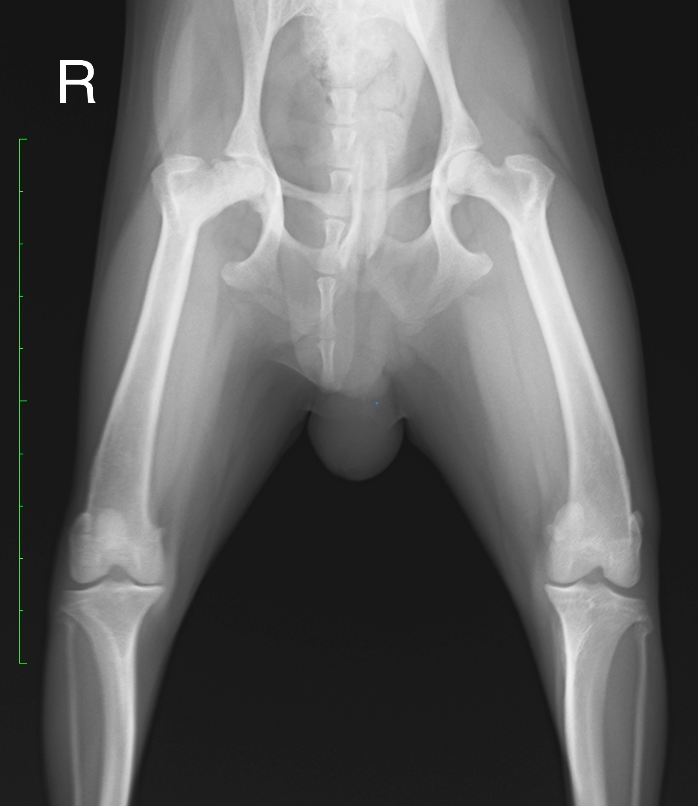

来院時のレントゲン写真です。

右大腿骨の大腿骨頭の変形および扁平化が確認されました。